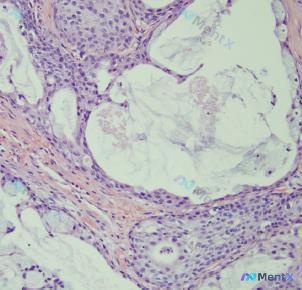

整理到一份挺有讨论/复盘价值的病理读片资料: 标本标注为 (B) 胎盘侧脐静脉,HE 染色 x100 倍。 镜下主要表现: - 背景是粉染均一状/细纤维状的基质,类似淀粉样变或玻璃样变;左上方可见一片深染粉红区,提示出血或富含蛋白的渗出/坏死 - 细胞较小,呈圆形/卵圆形,缺乏显著异型性,排列呈“蜂...